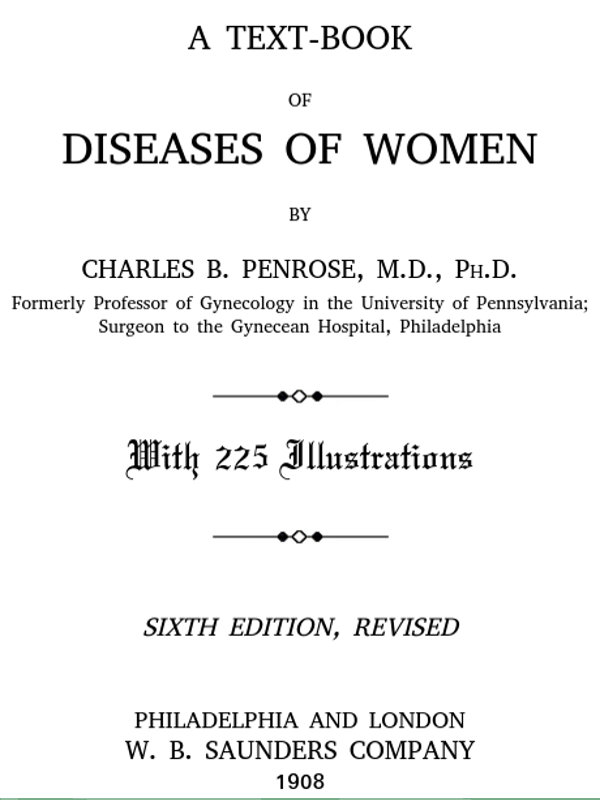

Examination of External Genitals and Pelvic Structures.—To examine the external organs of generation and the pelvic viscera the woman should be placed upon a table. In some cases the physician may be obliged, for want of proper facilities or on account of the physical condition of the patient, to make his examination upon a bed. Such an examination, however, is never so satisfactory or so thorough as the examination made with the woman upon the examining-table. A great number of gynecological tables have been introduced. The one which seems to the writer the best, on account of its simplicity and the perfect relaxation of the abdominal muscles furnished by it, is shown in the accompanying illustration (Fig. 1). It is a plain wooden table, at the foot of which are attached the upright supports for holding the stirrups for the feet, such as have been devised by Dr. Edebohls. By this arrangement the feet and legs are supported without any effort on the part of the woman; when the buttocks are drawn well down to the foot of the table there is a certain amount of flexion 23 of the pelvis upon the trunk, and the most complete attainable relaxation of the abdominal muscles is secured.

Fig. 1.—Woman in the dorsal position with feet supported in Edebohls’ stirrups.

For operation upon the perineum the woman should be placed in the dorso-sacral position (Fig. 1, page 23).